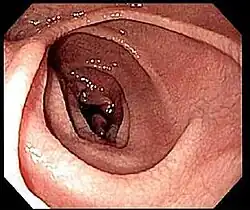

Geralmente é realizada uma biópsia do duodeno ou do jejuno. São recolhidas entre quatro e oito amostras de tecido, já que as áreas podem não ser afetadas por igual e se a amostra for recolhida a partir de uma área saudável pode dar origem a falsos negativos.[39]

Na maior parte das pessoas com doença celíaca, o intestino delgado apresenta-se normal durante uma endoscopia. No entanto, existem cinco observações endoscópicas que sugerem doença celíaca: pregas mucosas serrilhadas, padrão em mosaico da mucosa (semelhante ao padrão de lama seca), proeminência dos vasos sanguíneos da submucosa e padrão nodular da mucosa.[67]

Até à década de 1970, as biópsias eram realizadas com cápsulas de metal ligadas a um dispositivo de sucção. A cápsula era engolida e transitava até ao intestino delgado. Após ser confirmada a sua posição através de raio X, era aplicada sucção para recolher parte da parede intestinal para o interior da cápsula. Este método foi em grande parte substituído pela endoscopia de fibra ótica, com maior sensibilidade e menor taxa de erro.[68]